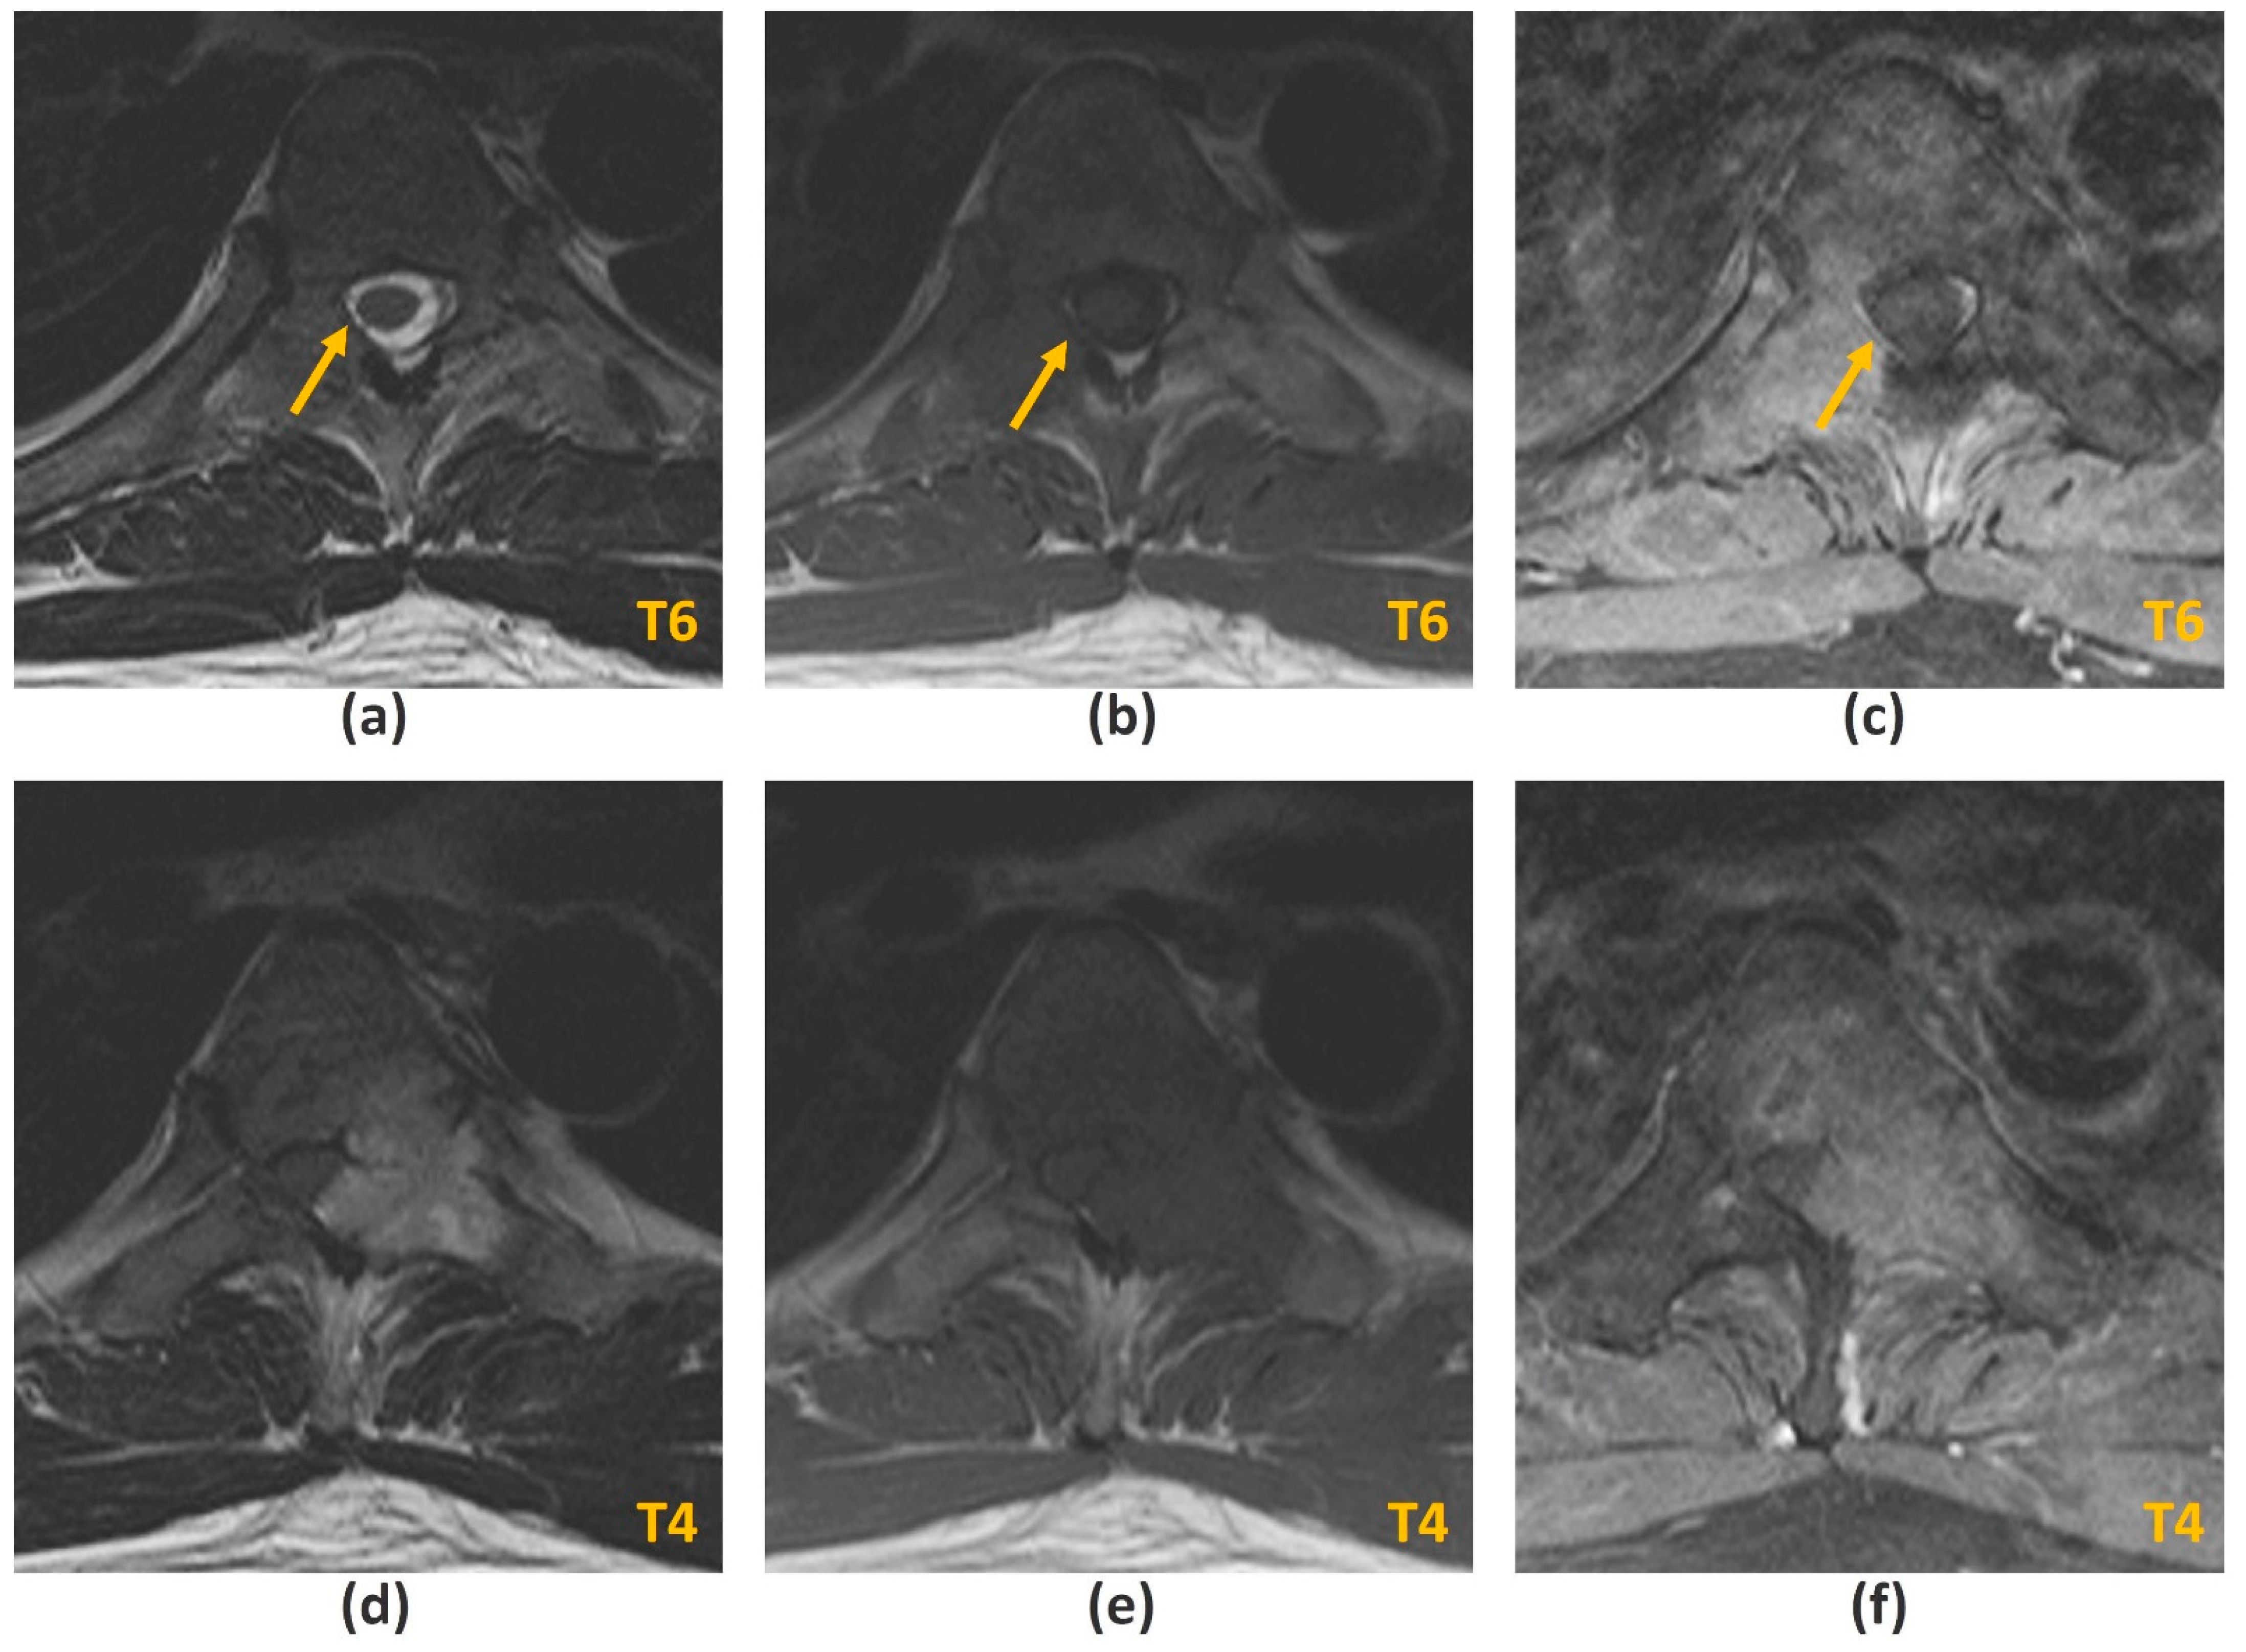

- Hallinan, J.T.P.D.; Zhu, L.; Zhang, W.; Lim, D.S.W.; Baskar, S.; Low, X.Z.; Yeong, K.Y.; Teo, E.C.; Kumarakulasinghe, N.B.; Yap, Q.V.; et al. Deep Learning Model for Classifying Metastatic Epidural Spinal Cord Compression on MRI. Front. Oncol. 2022, 12, 849447. [Google Scholar] [CrossRef]